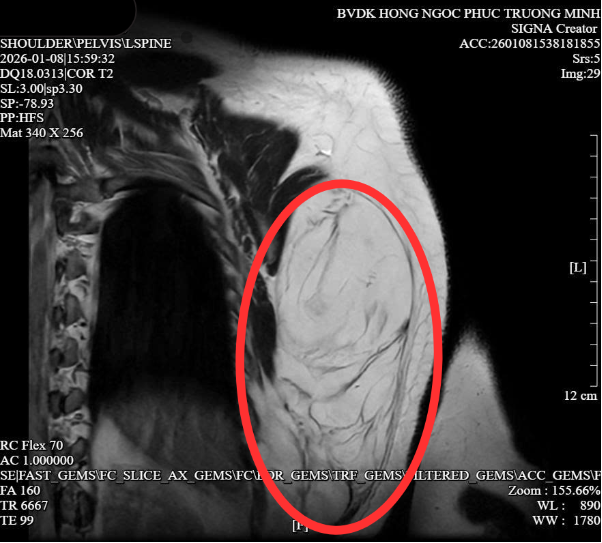

Qua các kết quả chẩn đoán hình ảnh, ThS.BS Đỗ Anh Tuấn – Chuyên khoa Ngoại Ung bướu xác định khối u mỡ dưới da vùng lưng trái với kích thước khoảng 11,8 x 12cm, chiều dài lớn nhất lên tới 22cm. May mắn, khối u chưa xâm lấn vào các lớp cơ hay xương sườn, giúp bảo tồn tương đối các cấu trúc giải phẫu quan trọng. Đây được xem là yếu tố then chốt để các bác sĩ chỉ định phẫu thuật bóc tách triệt để, hạn chế biến chứng và nguy cơ tái phát.

Hình ảnh MRI cho thấy khối u mỡ kích thước lớn vùng ngực – lưng trái người bệnh